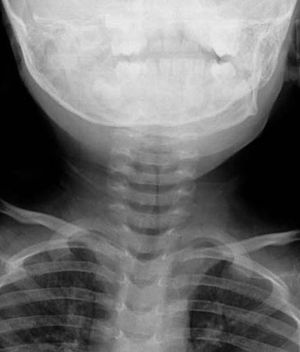

Which sign it is ?

Steeple sign??

Yeah right dr. ))